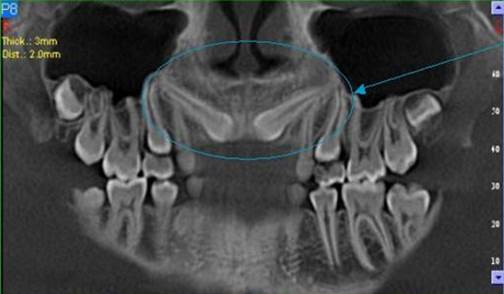

3D DVT - NewTom

Je speciální zubní digitální tříprostorový tomograf (3D), který umožňuje na základě jediného

snímkování vytvořit všechny typy RTG zobrazení, které jsou pro lékaře potřebné. Díky používané technologii tzv. „kuželového paprsku“ a speciálním senzorům je

výrazně zmenšená dávka záření - o více jak 80% proti klasickému CT vyšetření. To je významné zejména u dětí. Pomocí tohoto přístroje je možné zjisti skutečnou situaci v čelistních kostech pacienta tedy množství kosti - můžeme změřit skutečnou šířku i výšku kosti, i kvalitu kosti (hustotu) v místě uvažované implantace. 3D (tříprostorové) zobrazení umožňuje zvýšit prostorovou představu operatéra ještě před vlastní operací a zároveň pacientovi lépe objasnit a ukázat oblast plánovaného zavedení implantátu.

Pacient „neumí číst“ RTG snímky, ale díky 3D zobrazení vidí „svoji skutečnou čelist“

- např. jak je nízká či úzká, vidí průběh nervu nebo velikost čelistní dutiny, což mu umožní i pochopení nutnosti v některých případech provést pomocné zákroky ještě před vlastním zavedením implantátu (viz. kostní štěp, sinus lift, kostní granulát...).

Vyšetření pomocí tohoto přístroje používáme i ve stomatochirurgii (zlomeniny čelistí, zuby moudrosti, cysty, onemocnění čelistního kloubu), ortodoncii (retinované zuby, nadpočetné zuby), parodontologii atd.